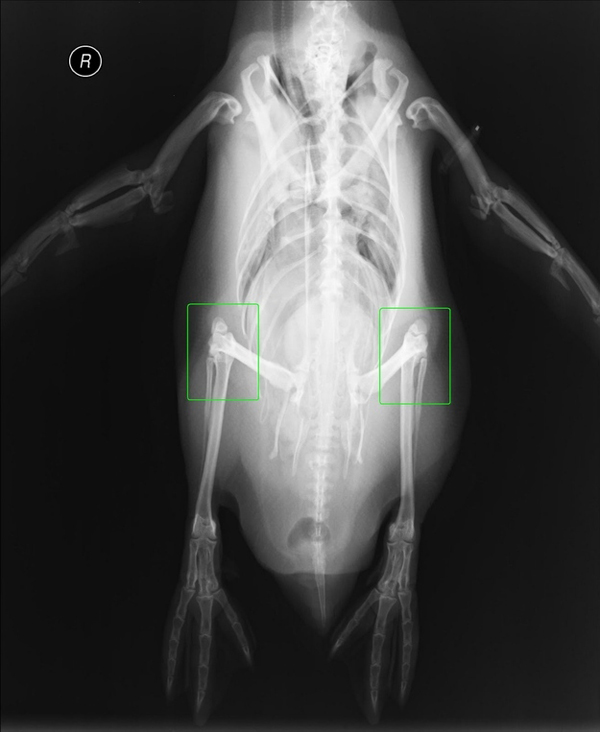

Na röntgenovýh snímkach uvidíte, čo skrývajú pred svetom.

Áno vidíte dobre. Hoci sa na prvý pohľad zdá, že tučniaky majú dolné končatiny obmedzené len na chodidlá, pod povrchom sa skrýva ich zvyšná časť.

Takéto dlhé nôžky má tučniak v skutočnosti.